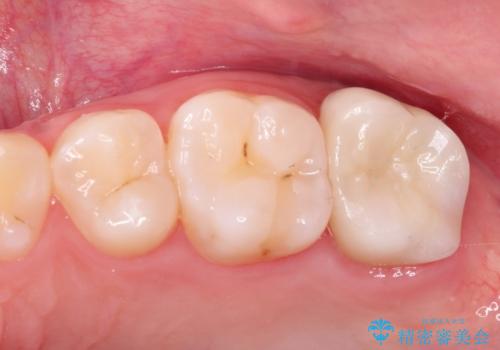

奥歯がズキズキ痛い 根管治療

担当医 河口智英